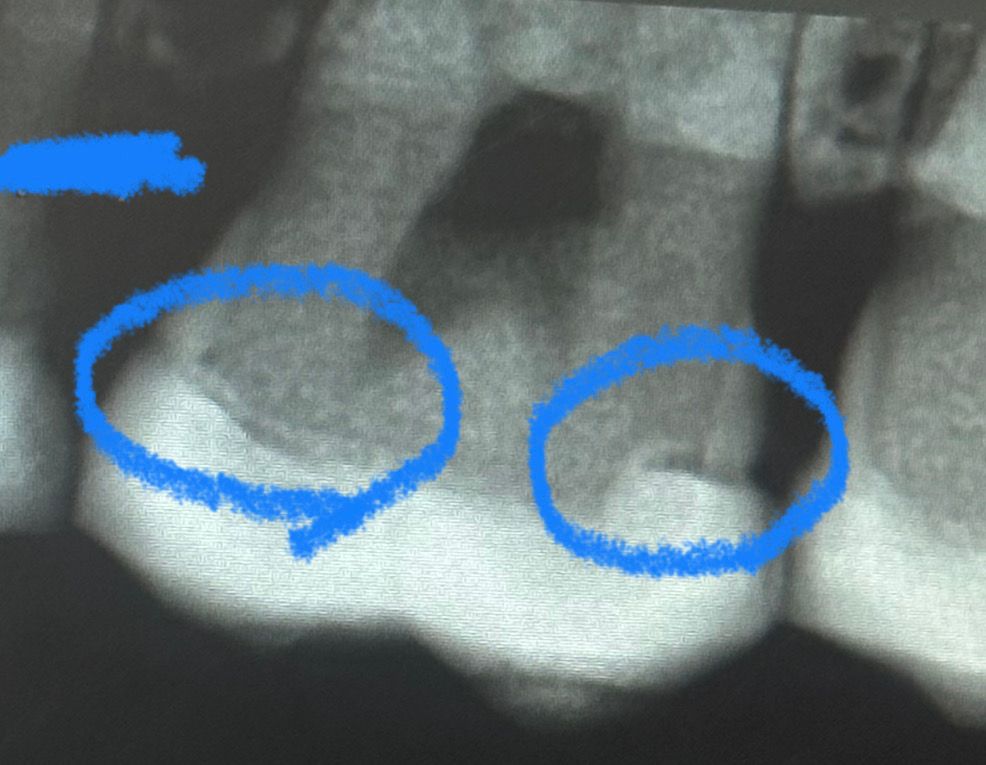

이 정도 인레이 틈 재치료해야할까요?

이 정도 인레이 틈이면 재치료 해야할까요??

그리고 이게 인레이 틈인건지 아니면 2차 충치인건지도 궁금합니다

틈이 생기면 그 안으로 음식물이 들어갈 수도 있는걸까요?

인레이를 했을 경우 치아 사이에 틈이 생길 수 있습니다. 이런 틈은 방사선 사진상으로 투명하게 보일 수 있지만 실질적으로 재료가 들어가 있는 경우도 있습니다. 신경이 쓰인다면 보철물을 다시 제작해 주는 것이 좋을 수 있습니다.

틈일수도 있고 시멘갭(치아와 인레이 사이 접착제가 투과상으로 보이는 것) 일 수도 있습니다. 오래되지 않은 인레이라면 시멘갭일 것 같습니다.